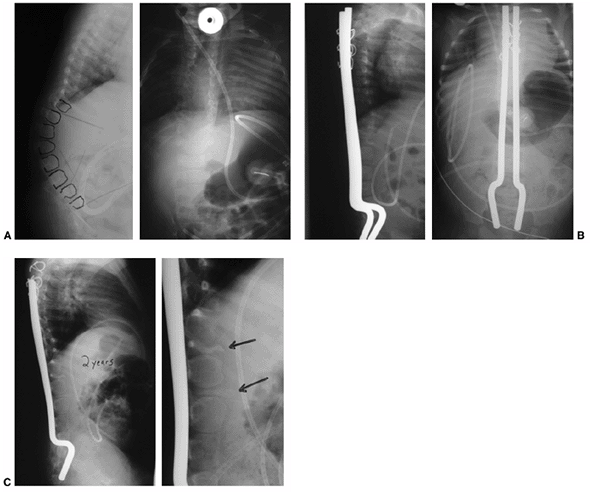

Figure 16.12 A: Anteroposterior and lateral radiographs of an 8-month-old infant with thoracic level of paralysis and C-shaped kyphosis. B:

Anteroposterior and lateral radiographs after decancellation of two vertebral bodies above and below the apex with posterior instrumentation. Rods are placed into the S1 foramen and fixed proximally with sublaminar wires in an extraperiosteal fashion. The rods are left long to allow for continued spine growth. C: Follow-up radiographs at 2 years demonstrate reduction of kyphosis and growth of the spine away from the rods proximally. Consolidation of the egg-shelled vertebrae are noted (arrows). |